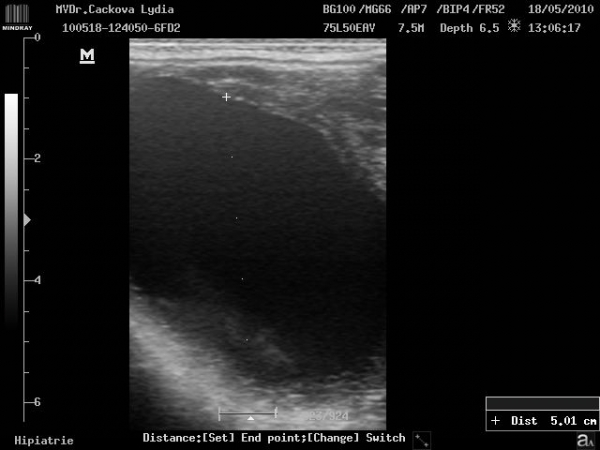

Volně pohyblivý lipom v podkoží klisny haflinga

Podotrochleóza